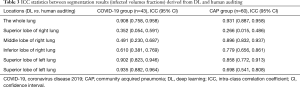

We also investigated the percentage of lung involvement in varying CT attenuation value ranges and observed that the highest proportion of lesions in the COVID-19 group were in the CT value of (–470, –370) HU, and of (30 to 60) HU in the CAP group. Significant differences were observed between the 2 groups for all CT value ranges (P<0.05) except for the range of (–370, –270). As Table 3 shows, we also investigated the intra-class correlation coefficient (ICC) statistics between the segmentation results (infected volume fractions) derived from DL alone and human auditing. The results showed that there was good consistency in the volume proportion of the total lung infection between the groups (Table 3).

Full table